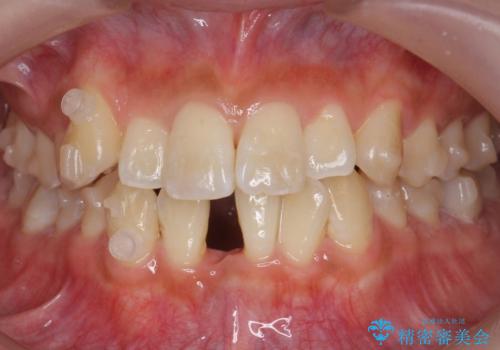

八重歯 インビザラインで抜歯矯正 ただし1本のみの抜歯で済みます

- 八重歯を治したいと来院。

古典的な治し方ですと上下左右4本抜歯してワイヤー矯正です。

今回は口元も出ていないうえに、右上のみの八重歯のため奥歯を後ろに下げて治療しました。

ただし、下の前歯は入りきらない為1本のみ抜歯しています。

右上の犬歯をおろしてくるのに、顎間ゴムを使用しています。